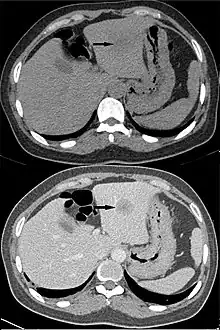

Angiography

CT angiography is a contrast CT taken at the location and corresponding phase of the blood vessels of interest, in order to detect vascular diseases. For example, an abdominal aortic angiography is taken in the arterial phase in the abdominal level, and is useful to detect for example aortic dissection.[10]